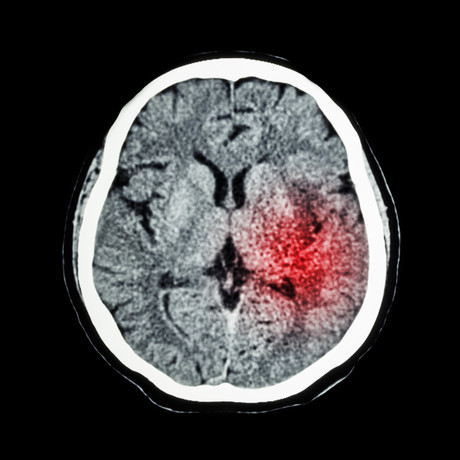

Current stroke guidelines limit the time to use clot-busting drugs to within 4.5 hours after the onset of stroke; but this new study found that extending this by up to nine hours after a stroke — in suitable cases — resulted in a higher percentage of patients with no or minimal deficits, compared with placebo. There were more cases of bleeding in the brain with the treatment than placebo.

The EXTEND randomised clinical trial found the initial window of 4.5 hours from symptom onset could now be pushed to nine hours given solid evidence of ‘brain to save’ on advanced brain imaging.

“These results shift the stroke paradigm from using a clock to determine eligibility for clot-dissolving treatment to using brain imaging to identify whether there is brain tissue that can be saved in the individual patient,” A/Prof Ma said.